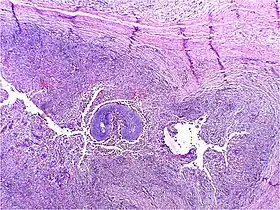

Актиноміко́з (грец. ακτις — промінь і μυκης — гриб) — хронічне захворювання людини та деяких сільськогосподарських тварин, яке спричинюють особливі бактерії актиноміцети, що раніше були віднесені до патогенних грибів.

Виникнення пухлиноподібних запальних утворень (інфільтратів дерев'янистої щільності (англ. sulfur granules) синцево-червоного забарвлення в м'яких тканинах навколо щелеп, на шиї, рідше в легенях, у кишечнику та інших місцях. З часом відбувається утворення гною у вогнищах, розм'якшення, флуктуація, а потім розвиток нориць. Процес носить хронічний характер.

Гній містить велику кількість актиноміцетів.